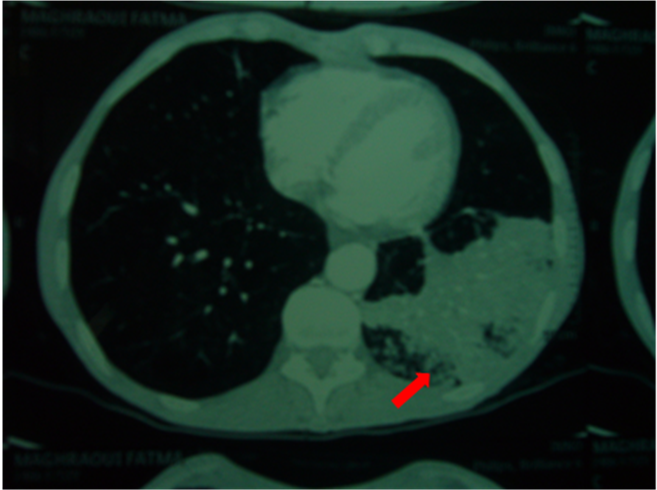

Fig 6